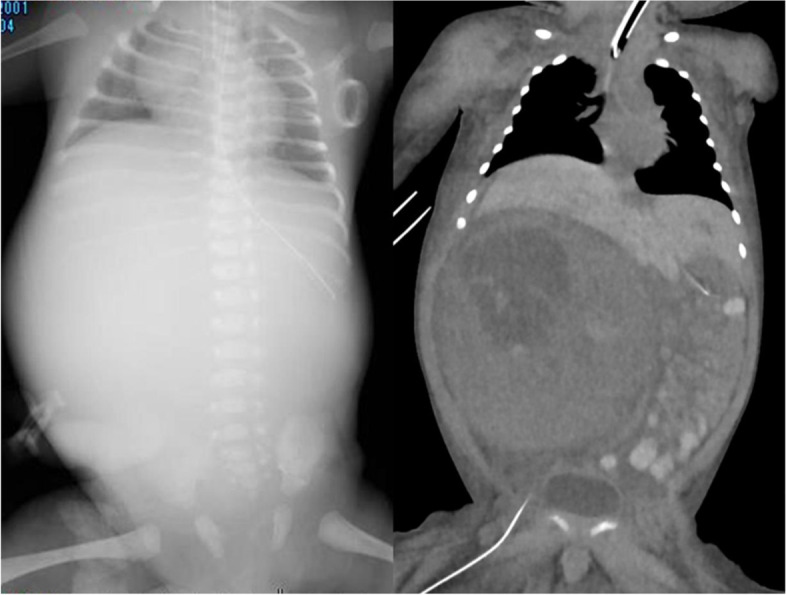

Fig. 2.

Chest and abdominal X-ray examination and contrast-enhanced CT at birth. Chest and abdominal X-ray showed elevation of the diaphragm and exclusion of the thorax. Contrast-enhanced CT showed an 80 × 100 mm mass in the right kidney that had an inhomogeneous contrast effect. The tumor excluded the liver to the cranial side and elevated the diaphragm